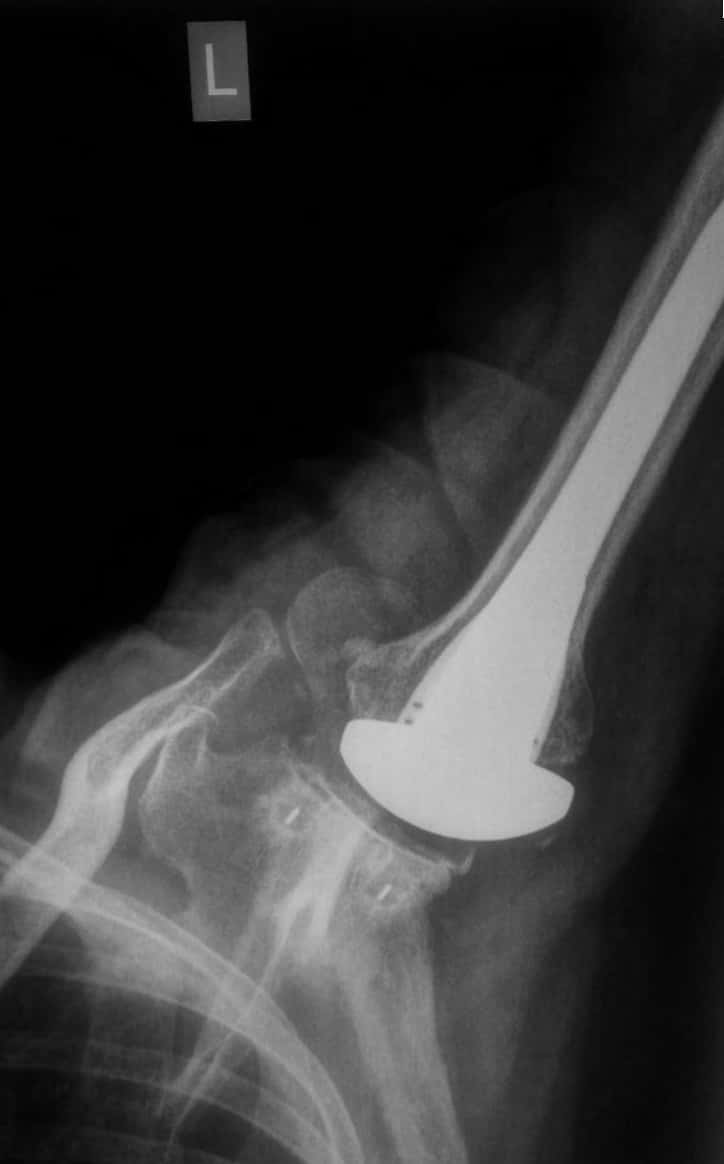

X-Rays

X-rays are imaging tests that create detailed pictures of dense structures, like bone. They can help distinguish among various forms of arthritis.X-rays of an arthritic shoulder will show a narrowing of the joint space, changes in the bone, and the formation of bone spurs (osteophytes).

Shoulder joint replacement (arthroplasty). Advanced arthritis of the glenohumeral joint can be treated with shoulder replacement surgery, in which the damaged parts of the shoulder are removed and replaced with artificial components, called prosthesis, just like a knee replacement which is indeed more common and more familiar for the patient!!

Complete wear or loss of normal smooth cartilage over the humeral head (Ball), Damaged cartilage over glenoid (socket), Replaced socket, replaced ballthis is how the replaced shoulder typically looks on an x ray!!